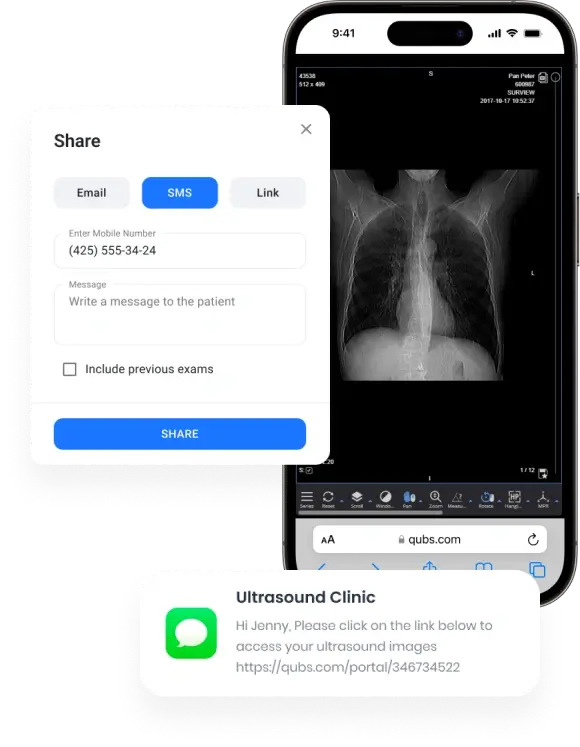

Facilitate real-time sharing and access to patient images and reports from anywhere, fostering better collaboration among healthcare professionals.

Works anywhere

Allow referrers and specialists to access images and reports on both desktop and mobile without any need for installations.